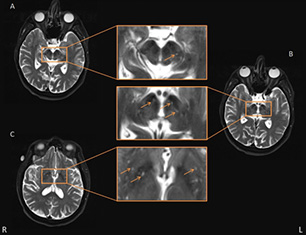

Figure 2

Representative axial T2-weighted images showing basal ganglia (BG) and midbrain perivascular space (PVS). Some typical PVS are indicated by the orange arrow. Panels (A,B) are two consecutive layers showing PVS in the midbrain, in which the PVS in panel (A) is continuous to the rightmost PVS in panel (B), and the PVS is shown passing through the SN. The other PVS in panel (B) were also deemed adjacent to SN. Panel (C) shows the axial slice which had the most PVS in the BG area.